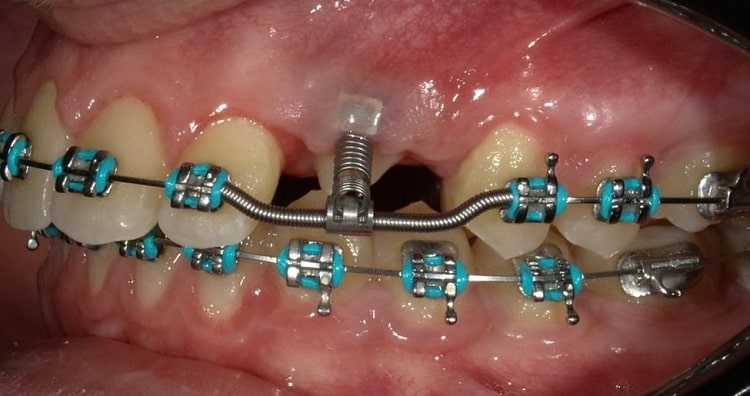

در برخی موارد ممکن است مجبور شوید از نوعی پوشش مخصوص فک استفاده کنید یا پینهای کوچکی را به طور موقت در فک خود قرار دهید و همچنین از بریس استفاده کنید. اگر دندانهای شما خیلی نزدیک به هم هستند و باعث نامرتبی و روی هم قرار گرفتن آنها میشوند ممکن است به عنوان بخشی از درمان لازم باشد برخی از آنها را بکشید.

ارتودنسی برای دندانهای نیش نهفته

بریسها میتوانند دندان نیش نهفته را به موقعیت صحیح خود بکشند. دندان در حالت عمودی و در موقعیت صحیح میتواند به عملکرد گاز زدن و جویدن کمک کند.